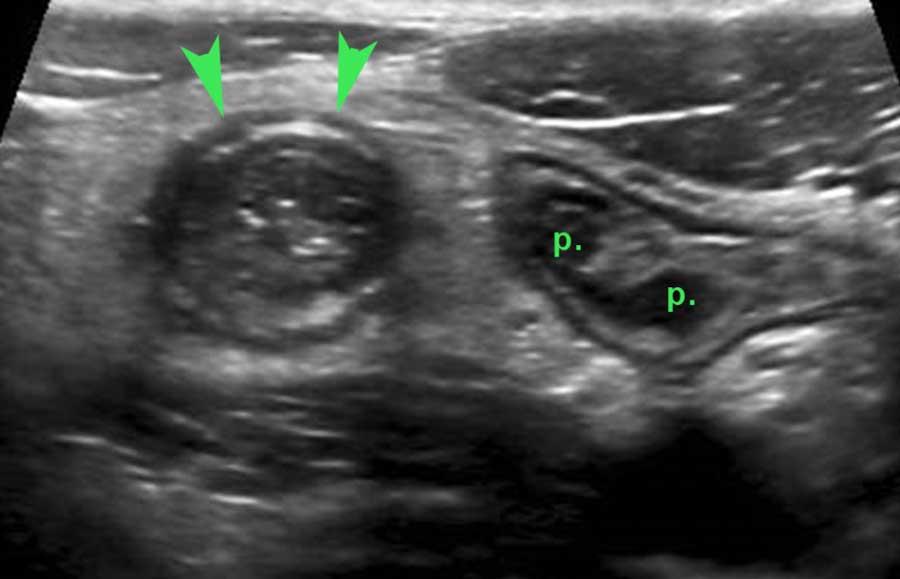

Ở người thanh niên 15 tuổi này bị viêm ruột thừa cấp tính (đầu mũi tên), vẫn còn các mảng Peyer (p.) nổi bật ở lớp niêm mạc sâu của hồi tràng đoạn cuối.